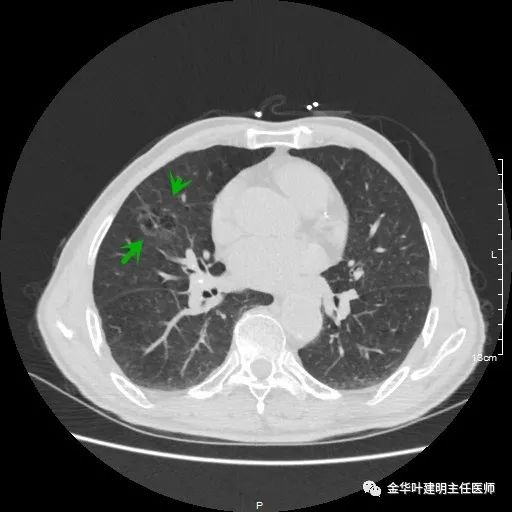

以上示右中叶病灶4。也是囊腔型病灶,病灶大,囊壁是磨玻璃密度,亦是较为典型的囊腔型肺癌影像。单病灶看,需中叶切除来治疗,因病灶3的存在,中叶切除可同时解决病灶3与病灶4。